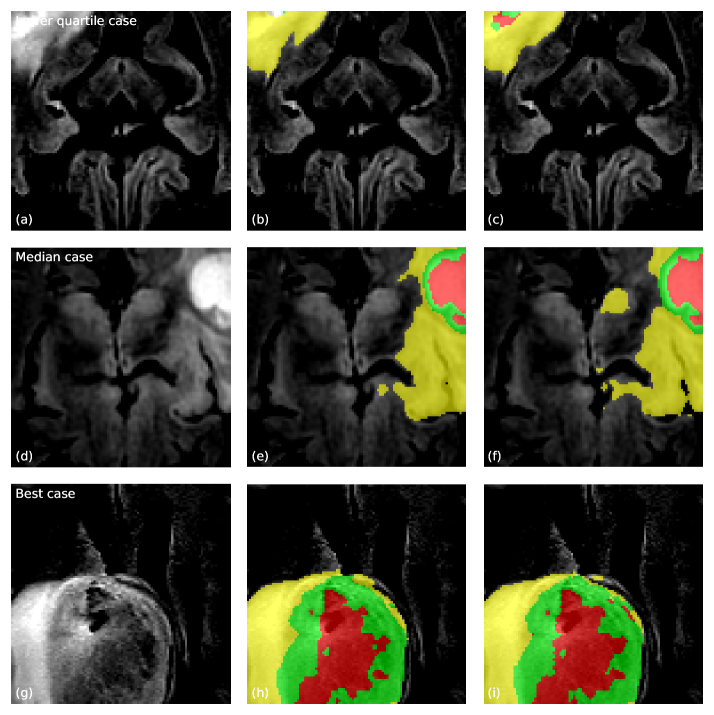

Refer to caption

Figure 5: Qualitative validation examples segmented by the proposed KLE-augmented 3D U-Net. Rows correspond to a lower-quartile case, a median case, and the best case according to the mean WT/TC/ET Dice on the validation crop. Columns display the FLAIR slice, the FLAIR slice with ground-truth labels, and the FLAIR slice with the predicted segmentation. Red = NCR/NET, yellow = ED, green = ET. Figure created by Anthony Joon Hur using Python.

Figure 5 shows three representative validation cases selected from the 187-case split. Each row corresponds to one case, ordered from a lower-quartile case (top row) to a median case (middle row) and a high-performing case (bottom row) according to their mean WT/TC/ET Dice on the validation crop. The columns display the FLAIR slice, the FLAIR slice overlaid with the ground-truth label map, and the FLAIR slice overlaid with the predicted segmentation. Red corresponds to NCR/NET, yellow to ED, and green to ET. These examples highlight that the KLE-augmented model usually captures the global tumor extent well, even for relatively difficult cases.